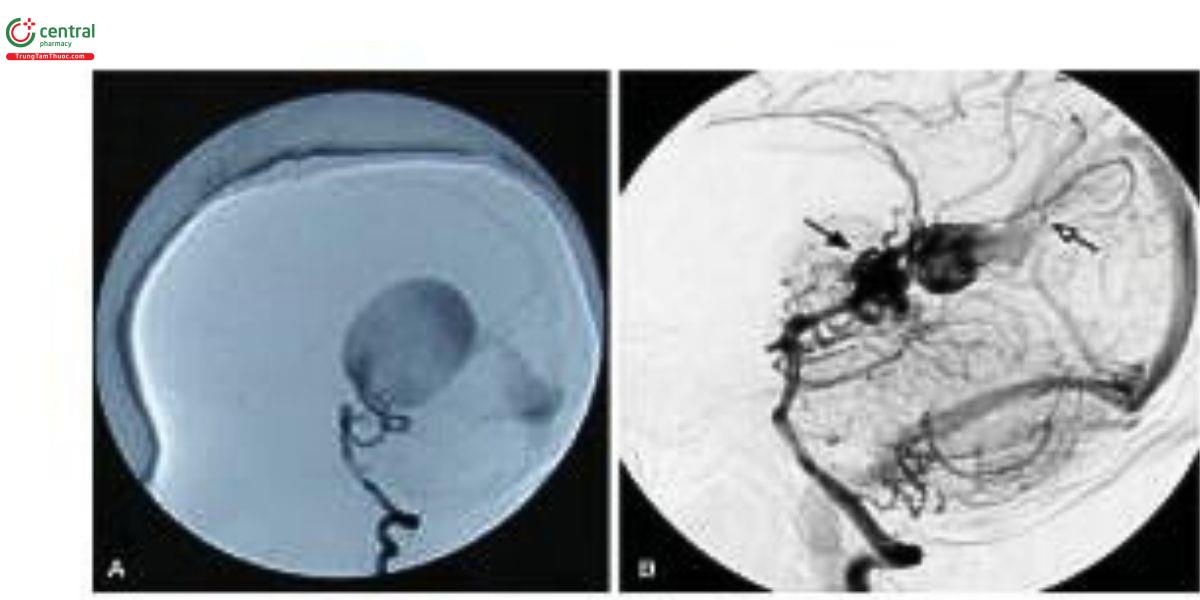

8 Điều trị nội mạch

Trường hợp đầu tiên được điều trị bằng nút mạch được Davis báo cáo vào năm 1950. Với sự phát triển của điều trị nội mạch, tỷ lệ tử vong đã giảm từ 60-82% xuống còn 11%. Mục tiêu của điều trị nội mạch là giảm dòng rò nội sọ hoặc thậm chí bịt tắc tất cả các lỗ rò (Hình 7). Thực tế, việc bịt tắc hoàn toàn không cần thiết, vì giảm khoảng một phần ba đến một nửa dòng rò là đủ để cải thiện các triệu chứng lâm sảng. Gần đây, một phân tích gộp cho thấy các biến chứng chính của điều trị nội mạch bao gồm thùng mạch não, chảy máu, thiều máu não, não úng thủy và thiều màu chỉ dưới. Việc phòng ngừa biến chứng phụ thuộc vào kỹ thuật nút mạch siêu chọn lọc đúng cách, lựa chọn vật liệu nút mạch và kỹ thuật chính xác, cũng như bảo tồn dẫn lưu tĩnh mạch não sâu bình thường. Ngoài ra, sự tồn tại của dẫn lưu bình thường giữa hệ tĩnh mạch sâu và VGAM cần được xem xét trước khi nút mạch để tránh các tác động bất lợi lên mạch máu não bình thường sau khi điều trị nội mạch. Mặc dù khó quan sát qua chụp mạch hoặc hình ảnh không xâm lấn, có thể do các yếu tố kỹ thuật và huyết động, dẫn lưu bình thường vẫn là yếu tố quan trọng trong kế hoạch điều trị.

Có hai phương pháp nút mạch, bao gồm đường động mạch và đường tĩnh mạch, trong đó đường động mạch được ưu tiên. Đường động mạch rồn có thể được sử dụng để nút mạch trong giai đoạn sơ sinh sớm, và động mạch đùi là lựa chọn thay thế khi động mạch rồn không khả dụng. Đối với đường tĩnh mạch, vẫn còn tranh cãi về kết quả của nút mạch đường tĩnh mạch. Trong các tài liệu trước đây, phương pháp này được coi là không khả thi do tăng biến chứng. Tuy nhiên, trong nghiên cứu gần đây, Orlov và cộng sự cho rằng đây là một phương pháp cứu vẫn an toàn và hiệu quả cho VGAM khí tiếp cận đường động mạch bị hạn chế. Ngoài ra, Meila và cộng sự mô tả một phương pháp kết hợp đường tĩnh mạch và động mạch, gọi là kỹ thuật "kissing microcatheter". Phương pháp này được xem là an toàn, với tỷ lệ biến chứng thấp và cải thiện kết quả tổng thể, đặc biệt ở trẻ sơ sinh có suy tim sung huyết. Các vật liệu nút mạch bao gồm cuộn coil, microballoon, N-butyl-cyanoacrylate (NBCA), Dung dịch Onyx, và copolymer ethylene vinyl alcohol. Ở loại đảm rối mạch mạc của VGAM, Onyx được khuyến nghị nhờ ưu điểm bịt tắc chắc chắn và ổn định hơn. Ở loại thành mạch, NBCA là vật liệu nút mạch được ưa chuộng do đặc tỉnh kết tủa nhanh và bám dính vào mạch. Ngoài ra, Joo và công sự lần đầu tiên báo cáo một bệnh nhân VGAM loại thành mạch được điều trị thành công bằng hệ thống Micro Vascular Plug, đây có thể là một lựa chọn tiểm năng